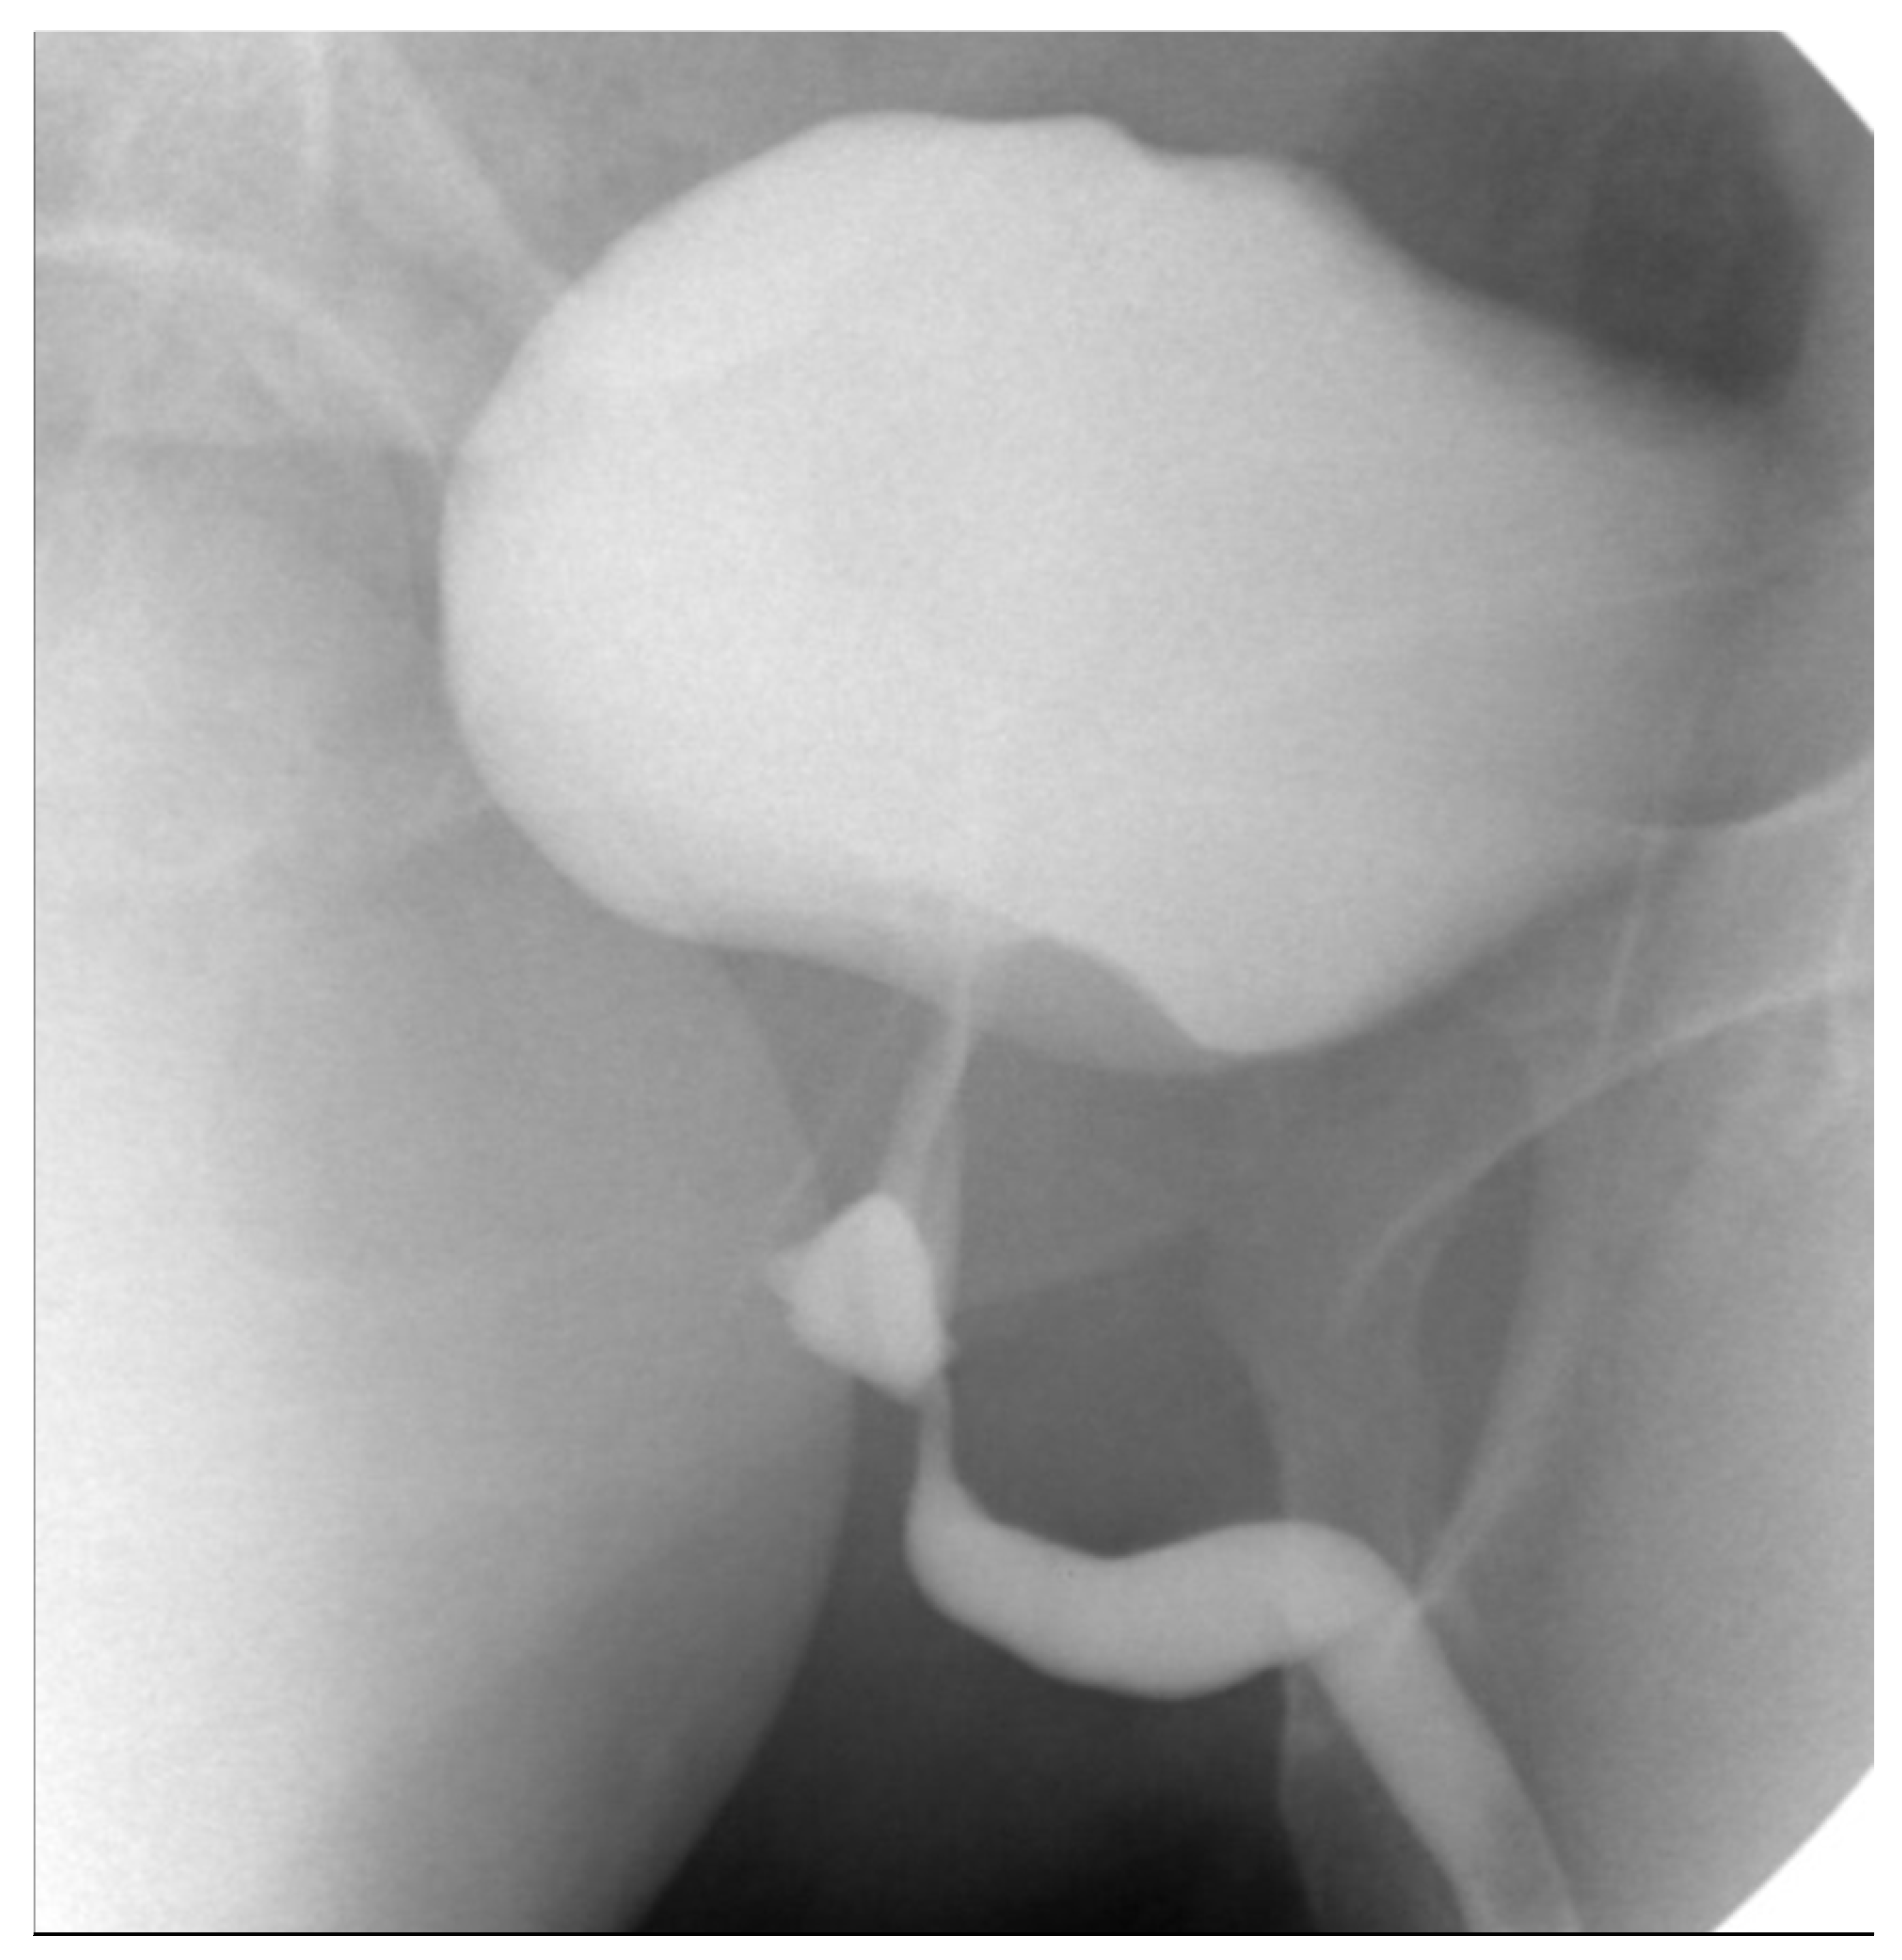

3.1. Case 1

3.2. Case 2